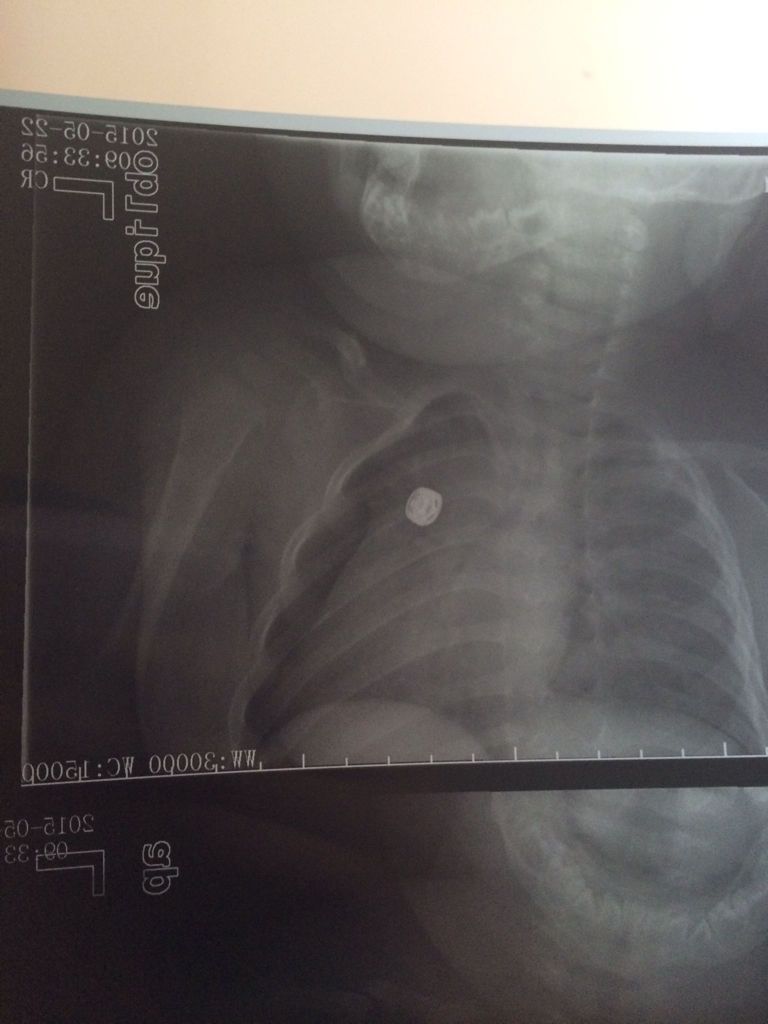

6个月宝宝左锁骨骨折,缠了八字绷带第二天左脸肿了怎么 点击展开 匿名用户 2015-05-23 11:47 为您推荐: 其他回答 考虑是绑带绑得太紧了导致颜面部的静脉回流无法回到心脏去的缘故,建议如果肿胀厉害需要返院适当的松一些绑带 笑天下美女 2015-05-23 12:35 相关问题 6个月宝宝从床上摔地上了,左侧朝下,左锁骨骨折了,医生缠了绷带,第二天左脸上 新生儿锁骨骨折错位了,当时拍片是发现,后来医生接了,还打了绷带,现在已经两周了,到医院复查后发现断 你好,我家宝宝17个月大了,锁骨骨折给她绑了8字绷带,绑了